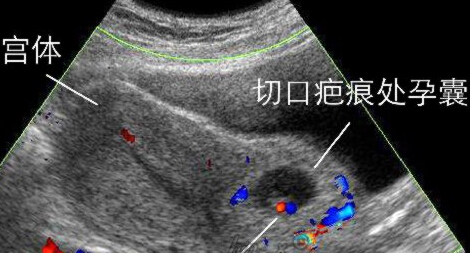

近年来发病率呈逐渐上升趋势的“瘢痕妊娠”是指有剖宫产史的孕妇,胚胎着床于子宫下段剖宫产切口瘢痕处,为剖宫产远期并发症之一。主要特点是停经后不规则阴道出血。易被误诊为不全流产而行刮宫术,从而导致致命性大出血。早期明确诊断很重要,经阴道B超是诊断瘢痕妊娠的主要手段。一旦确诊需立即住院治疗,治疗方案依据个体化原则。可以采用化疗药甲氨蝶呤,也可子宫动脉栓塞后行清宫术;也可选择手术切除局部病灶。